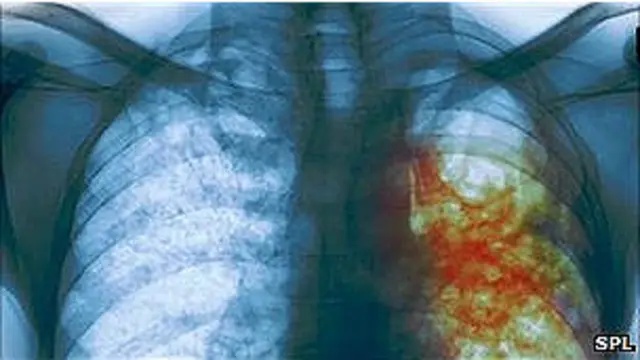

तपेदिक का वायरस आमतौर पर युवावस्था में हमला करता है. ये व्यक्ति के जीवन का सबसे क्रियाशील दौर होता है लेकिन फेफड़ों को निशाना बनाने वाली ये बीमारी इंसान को शारीरीक रुप से बेहद कमज़ोर और घातक बीमारियों के प्रति संवेदनशील बना देती है.

इमेज स्रोत, spl